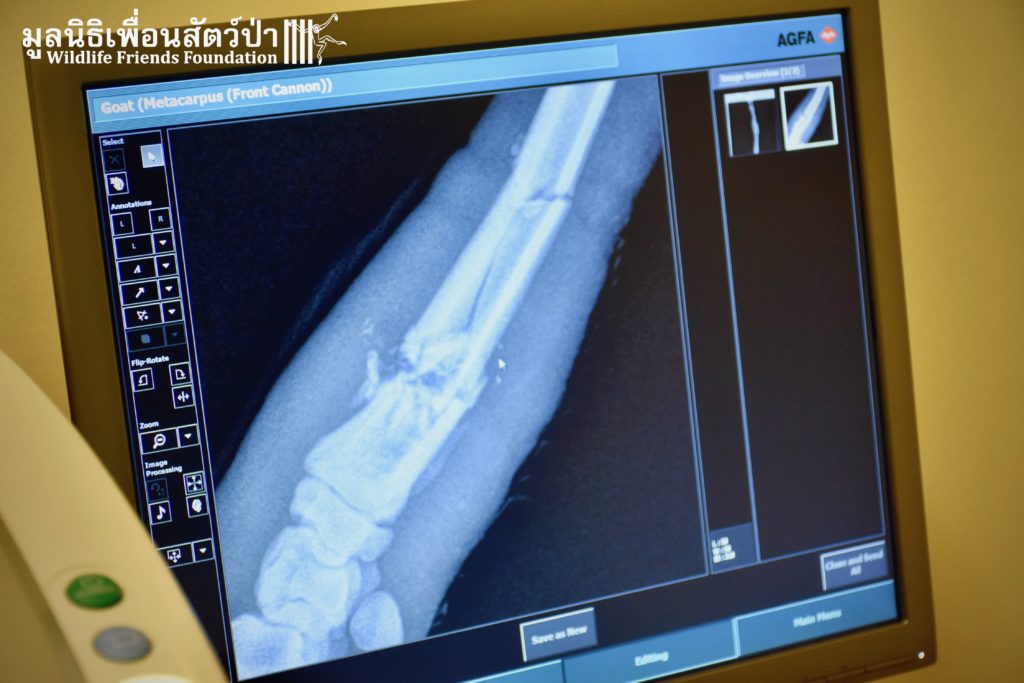

As you maybe already know, the WFFT Hospital this month became part of the first wildlife rescue center in Thailand to be equipped with its own digital X-ray suite.

This week an unfortunate sheep has been brought in for treatment with a terrible fractured front leg. She was unable to put weight on it. Thanks to our vets expertise and the X-ray it appeared that bones were clearly fractured on several places. Under the worried eyes of her owner, the WFFT Vet team provided the needed care for the poor animal. Soon she should be able to walk again!